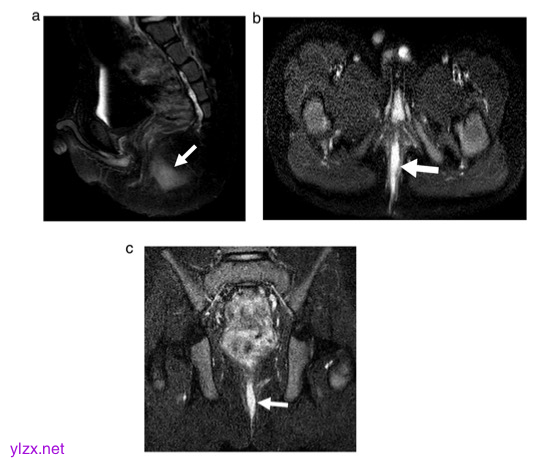

图 6岁男孩患有肛周克罗恩病。MRI脉冲序列包括(a)矢状面T2加权(T2W)快速自旋回波(FSE)脂肪饱和(FS), (b)轴向T2W FSE FS, (c)冠状面短tau反转恢复(STIR)。白色箭头显示后中线线状高信号异常,与肛周瘘一致。当使用Parks分类系统时,五位放射科医生将瘘管道描述为经括约肌,五位描述为括约肌间,三位描述为括约肌上